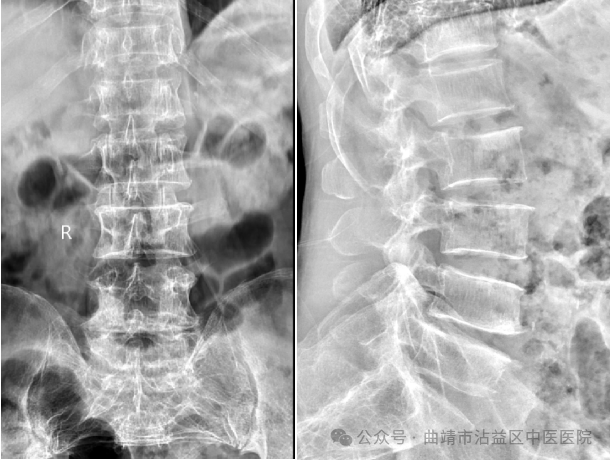

患者马某,男,56岁,因“右下肢反复麻木疼痛半年余”至沾益区中医医院就诊,收入我院骨伤科。入院后查体:右下肢麻木疼痛至足趾尖部,右下肢活动受限,右下肢直腿抬高试验阳性。患者手术指征明确,无明显手术禁忌,征得患者家属同意后,骨伤科医师团队决定为患者行L4-5;L5-S1椎间盘切除+椎间融合术,L4-S1钉棒系统内固定术。手术如期进行,在骨伤科医师团队的操作下,为患者顺利实施了椎间盘切除+椎间融合术。术后患者恢复良好,麻木疼痛感消失,3天即可下床活动。